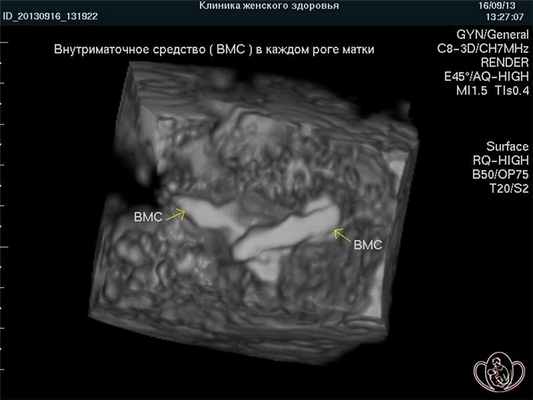

С уважением, Главный врач Курортной клиники женского здоровья канд. мед. наук О.Ю. Ермолаев.Вопрос: У меня матка двурогая. Подскажите, пожалуйста, могу ли я поставить ВМС, будет ли оно держаться? Заранее благодарна. М.К., г.Пятигорск.

Ответ: При двурогой матке ВМС требуется устанавливать в каждый рог при условии их полноценного развития. Эффективность ВМС не отличается от типичного случая.3D-фото: двурогая матка. Внутриматочное средство (ВМС) установлено в обоих рогах матки ![Двурогая матка]()